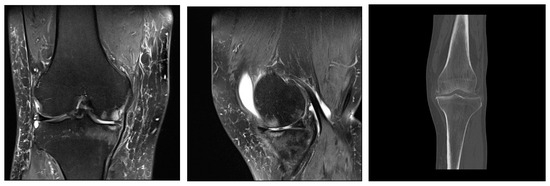

4. Radiological Characteristics of Osteoarthritis